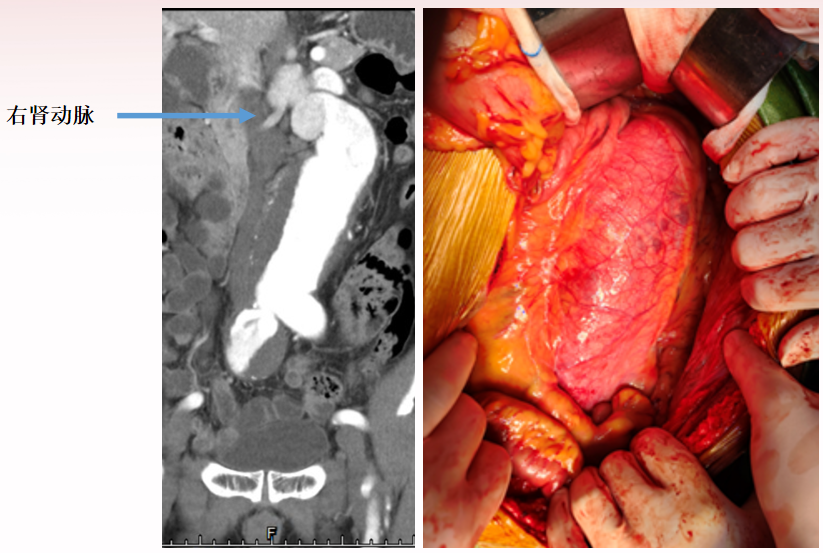

近肾腹主动脉瘤-1

男性,49岁

近肾腹主动脉瘤,左侧肾动脉受累,既往马凡综合征

手术方案:

腹主动脉瘤切除人工血管置换术 +左肾自体肾移植术

采用直筒型人工血管

术后6个月CTA

术后1年CTA

术后2年CTA